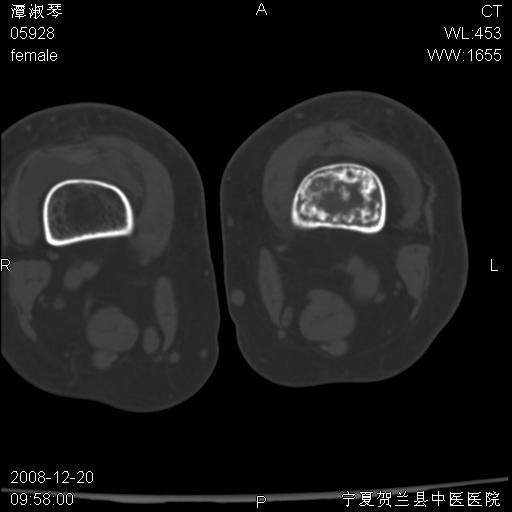

标题: CT17526:请各位看看是啥? [打印本页]

标题: CT17526:请各位看看是啥?

内生软骨瘤?骨梗死?

考虑内生软骨瘤可能性大

考虑-----骨梗死+退变

支持骨梗死,退行性骨关节病,膝关节积液.

考虑骨梗死可能性大

支持骨纤或内生软骨瘤或骨梗死,退行性骨关节病,膝关节积液.

左股骨下段骨梗死。双膝退变。

支持:内生软骨瘤或骨梗死!另:退行性骨关节病,膝关节积液。

左胫骨下端松质骨及髓腔内可见点片状高密度灶,骨皮质无明显膨胀及变薄。病变范围较长。支持骨梗死,退行性骨关节病,膝关节积液